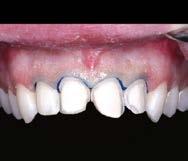

Estudio de caso

El paciente se presentó después de varios años de sufrir una herida traumática en sus dientes anterio res superiores. Las piezas 11 y 21 tenían varias fracturas, así como el borde incisal de la pieza 12. Por lo que él deseaba mejorar su estética bucal, y yo quería asegurarme de restaurar la funcionalidad y resisten cia también. El paciente necesitaba completar su tratamiento en un cor to periodo de tiempo, por ello debí realizar ajustes en mi flujo de traba jo. (Figura 1).

Durante la segunda cita le mostré al paciente su nuevo diseño de sonrisa en el modelo de encerado fabricado por Glidewell.

Cita 2. Aprobación del encerado de diagnóstico

Durante la segunda cita le mostré al paciente su nuevo diseño de sonrisa en el modelo de encerado fabricado

por Glidewell, permitiéndole exami nar el diseño estético de la restaura ción final propuesta (Figura 4).